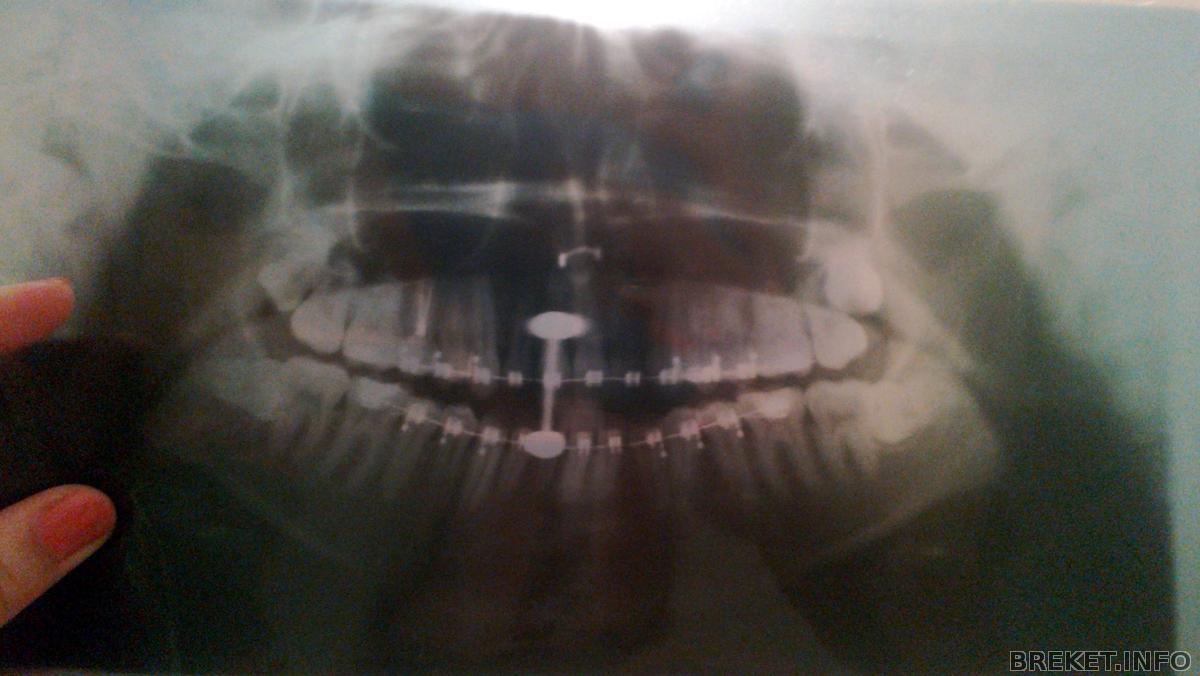

и мой офигенный снимок офигенных восьмёрок: